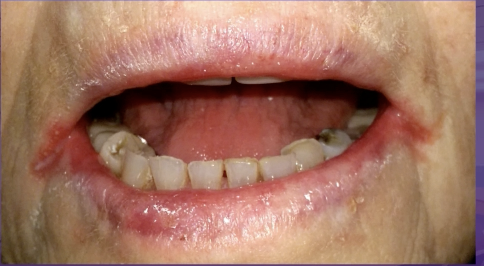

what is the cause of this lesion

primary herpes

herpangina

licking lower lip

erythema multiforme